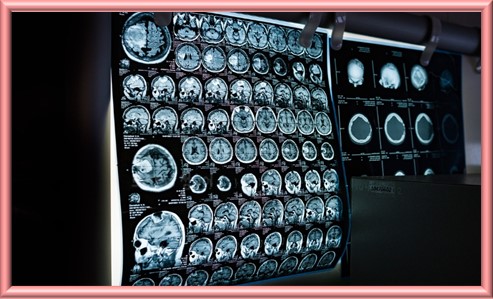

중추신경계 발달재활치료

중추신경계 발달 재활은 중추신경계 손상이나 발달 지연 때문인 신체적, 인지적, 정서적 문제를 치료하고 기능을 회복하는 학제적 접근 방식이다. 이 치료는 신경학적 재활의 중요한 부분으로, 어린이와 성인 모두에게 적용할 수 있으며 다양한 질병과 부상 상황에서 활용된다. 중추신경계 발달 재활은 신경 가소성을 기반으로 하며 손상된 뇌와 척수의 회복 잠재력을 극대화하고 환자의 삶의 질을 개선하는 데 중점을 둡니다.